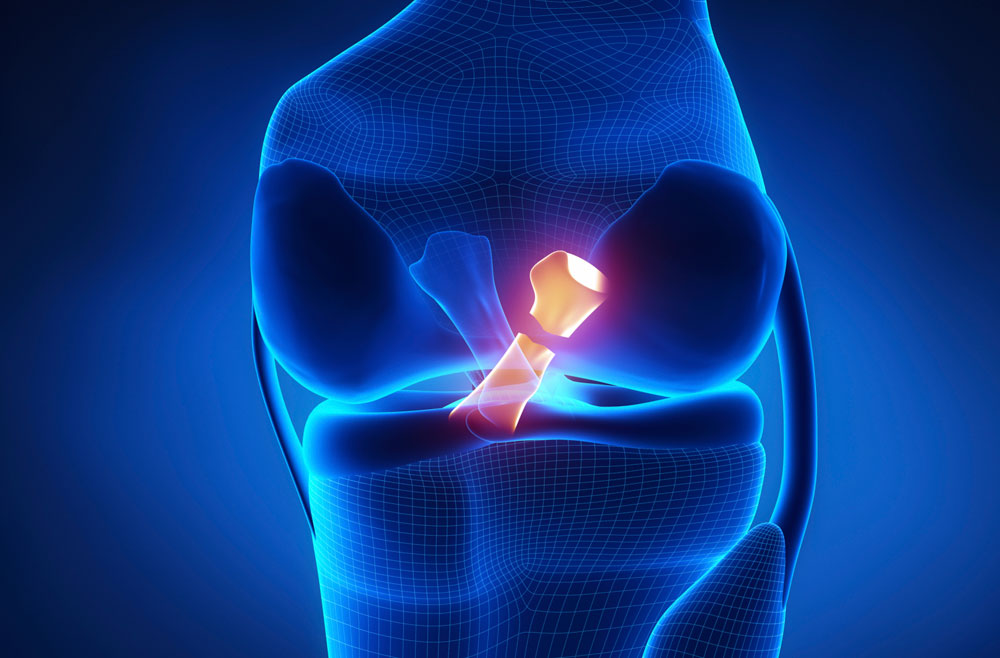

Dr. Ankur Singh is a highly experienced Senior Orthopedic Surgeon with over 15 years of expertise in Arthroscopy, Sports Medicine, Arthroplasty and Robotic Joint Replacement. He specializes in advanced knee, shoulder and hip surgeries, including primary, complex, and revision joint replacements, ligament reconstructions, cartilage restoration, osteotomy and joint preservation procedures.

Advanced 3D surgical mapping and robotic systems allow millimeter-level accuracy and optimized implant positioning.

Precise Orthopedic Care